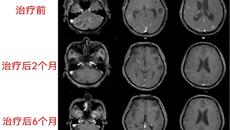

2021年初,家住南宁的陈老伯突然出现剧烈头痛,并伴有脑部昏沉感、行走不稳,起初陈老伯不以为意,认为是自己没休息好或受凉引起,可出乎他意料的是,头痛的症状竟一天比一天严重。1月9日,陈老伯终于无法忍受剧烈的痛楚,家人赶紧将他送至家附近的医院,经头颅CT检查,提示脑内多发囊实性病变,性质暂时不明,于是给他开了几天的对症口服药物,可陈老伯服药后头痛症状非但没有缓解,还出现了恶心、呕吐等症状。医院在给陈老伯...01.112022